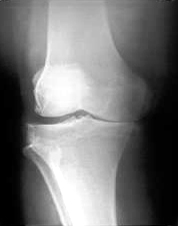

The x-ray below shows a right leg with a degenerated medial (inside) compartment. Notice how there is no space between the femur and the tibia. This bone on bone contact can be quite painful. The x-ray below shows a right leg with a degenerated medial (inside) compartment. Notice how there is no space between the femur and the tibia. This bone on bone contact can be quite painful.

Unicompartmental Osteoarthritis